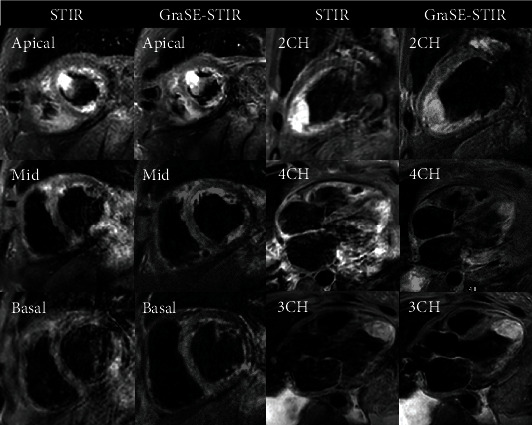

目的:本研究旨在评估基于梯度自旋回波(GraSE)的短头绪反转恢复(STIR)序列(GraSE-STIR)与基于传统涡轮自旋回波(TSE)的 STIR 序列相比在心血管磁共振(CMR)成像中的功效,特别关注图像质量、比吸收率(SAR)和图像采集时间:在一项前瞻性研究中,我们使用传统 STIR 和 GraSE-STIR 技术对 44 名正常志愿者和 17 名转诊为 CMR 成像的患者进行了检查。比较了两种序列的信噪比(SNR)、对比度-信噪比(CNR)、图像质量、T2 信号强度(SI)比、SAR 和图像采集时间:与传统 STIR 相比,GraSE-STIR 在图像质量(4.15 ± 0.8 vs. 3.34 ± 0.9,p = 0.024)和心脏运动伪影减少(53 例中有 7 例 vs. 18 例,p = 0.038)方面有明显改善。此外,在短轴平面上,GraSE-STIR 的采集时间(27.17 ± 3.53 对 36.9 ± 4.08 秒,p = 0.041)和局部躯干 SAR(p = 0.047)明显低于传统 STIR。然而,这两种序列在 T2 SI 比值(p = 0.141)、信噪比(p = 0.093)、CNR(p = 0.068)和 SAR(p = 0.071)方面没有明显差异:结论:与传统的 STIR 序列相比,GraSE-STIR 具有明显的优势,图像质量更高,运动伪影更少,采集时间更短。这些发现凸显了 GraSE-STIR 作为常规临床 CMR 成像的重要技术的潜力。

Results: GraSE-STIR showed significant improvements in image quality (4.15 ± 0.8 vs. 3.34 ± 0.9, p = 0.024) and cardiac motion artifact reduction (7 vs. 18 out of 53, p = 0.038) compared to conventional STIR. Furthermore, the acquisition time (27.17 ± 3.53 vs. 36.9 ± 4.08 seconds, p = 0.041) and the local torso SAR (<13% vs. <17%, p = 0.047) were significantly lower for GraSE-STIR compared to conventional STIR in short-axis plan. However, no significant differences were shown in T2 SI ratio (p = 0.141), SNR (p = 0.093), CNR (p = 0.068), and SAR (p = 0.071) between these two sequences.